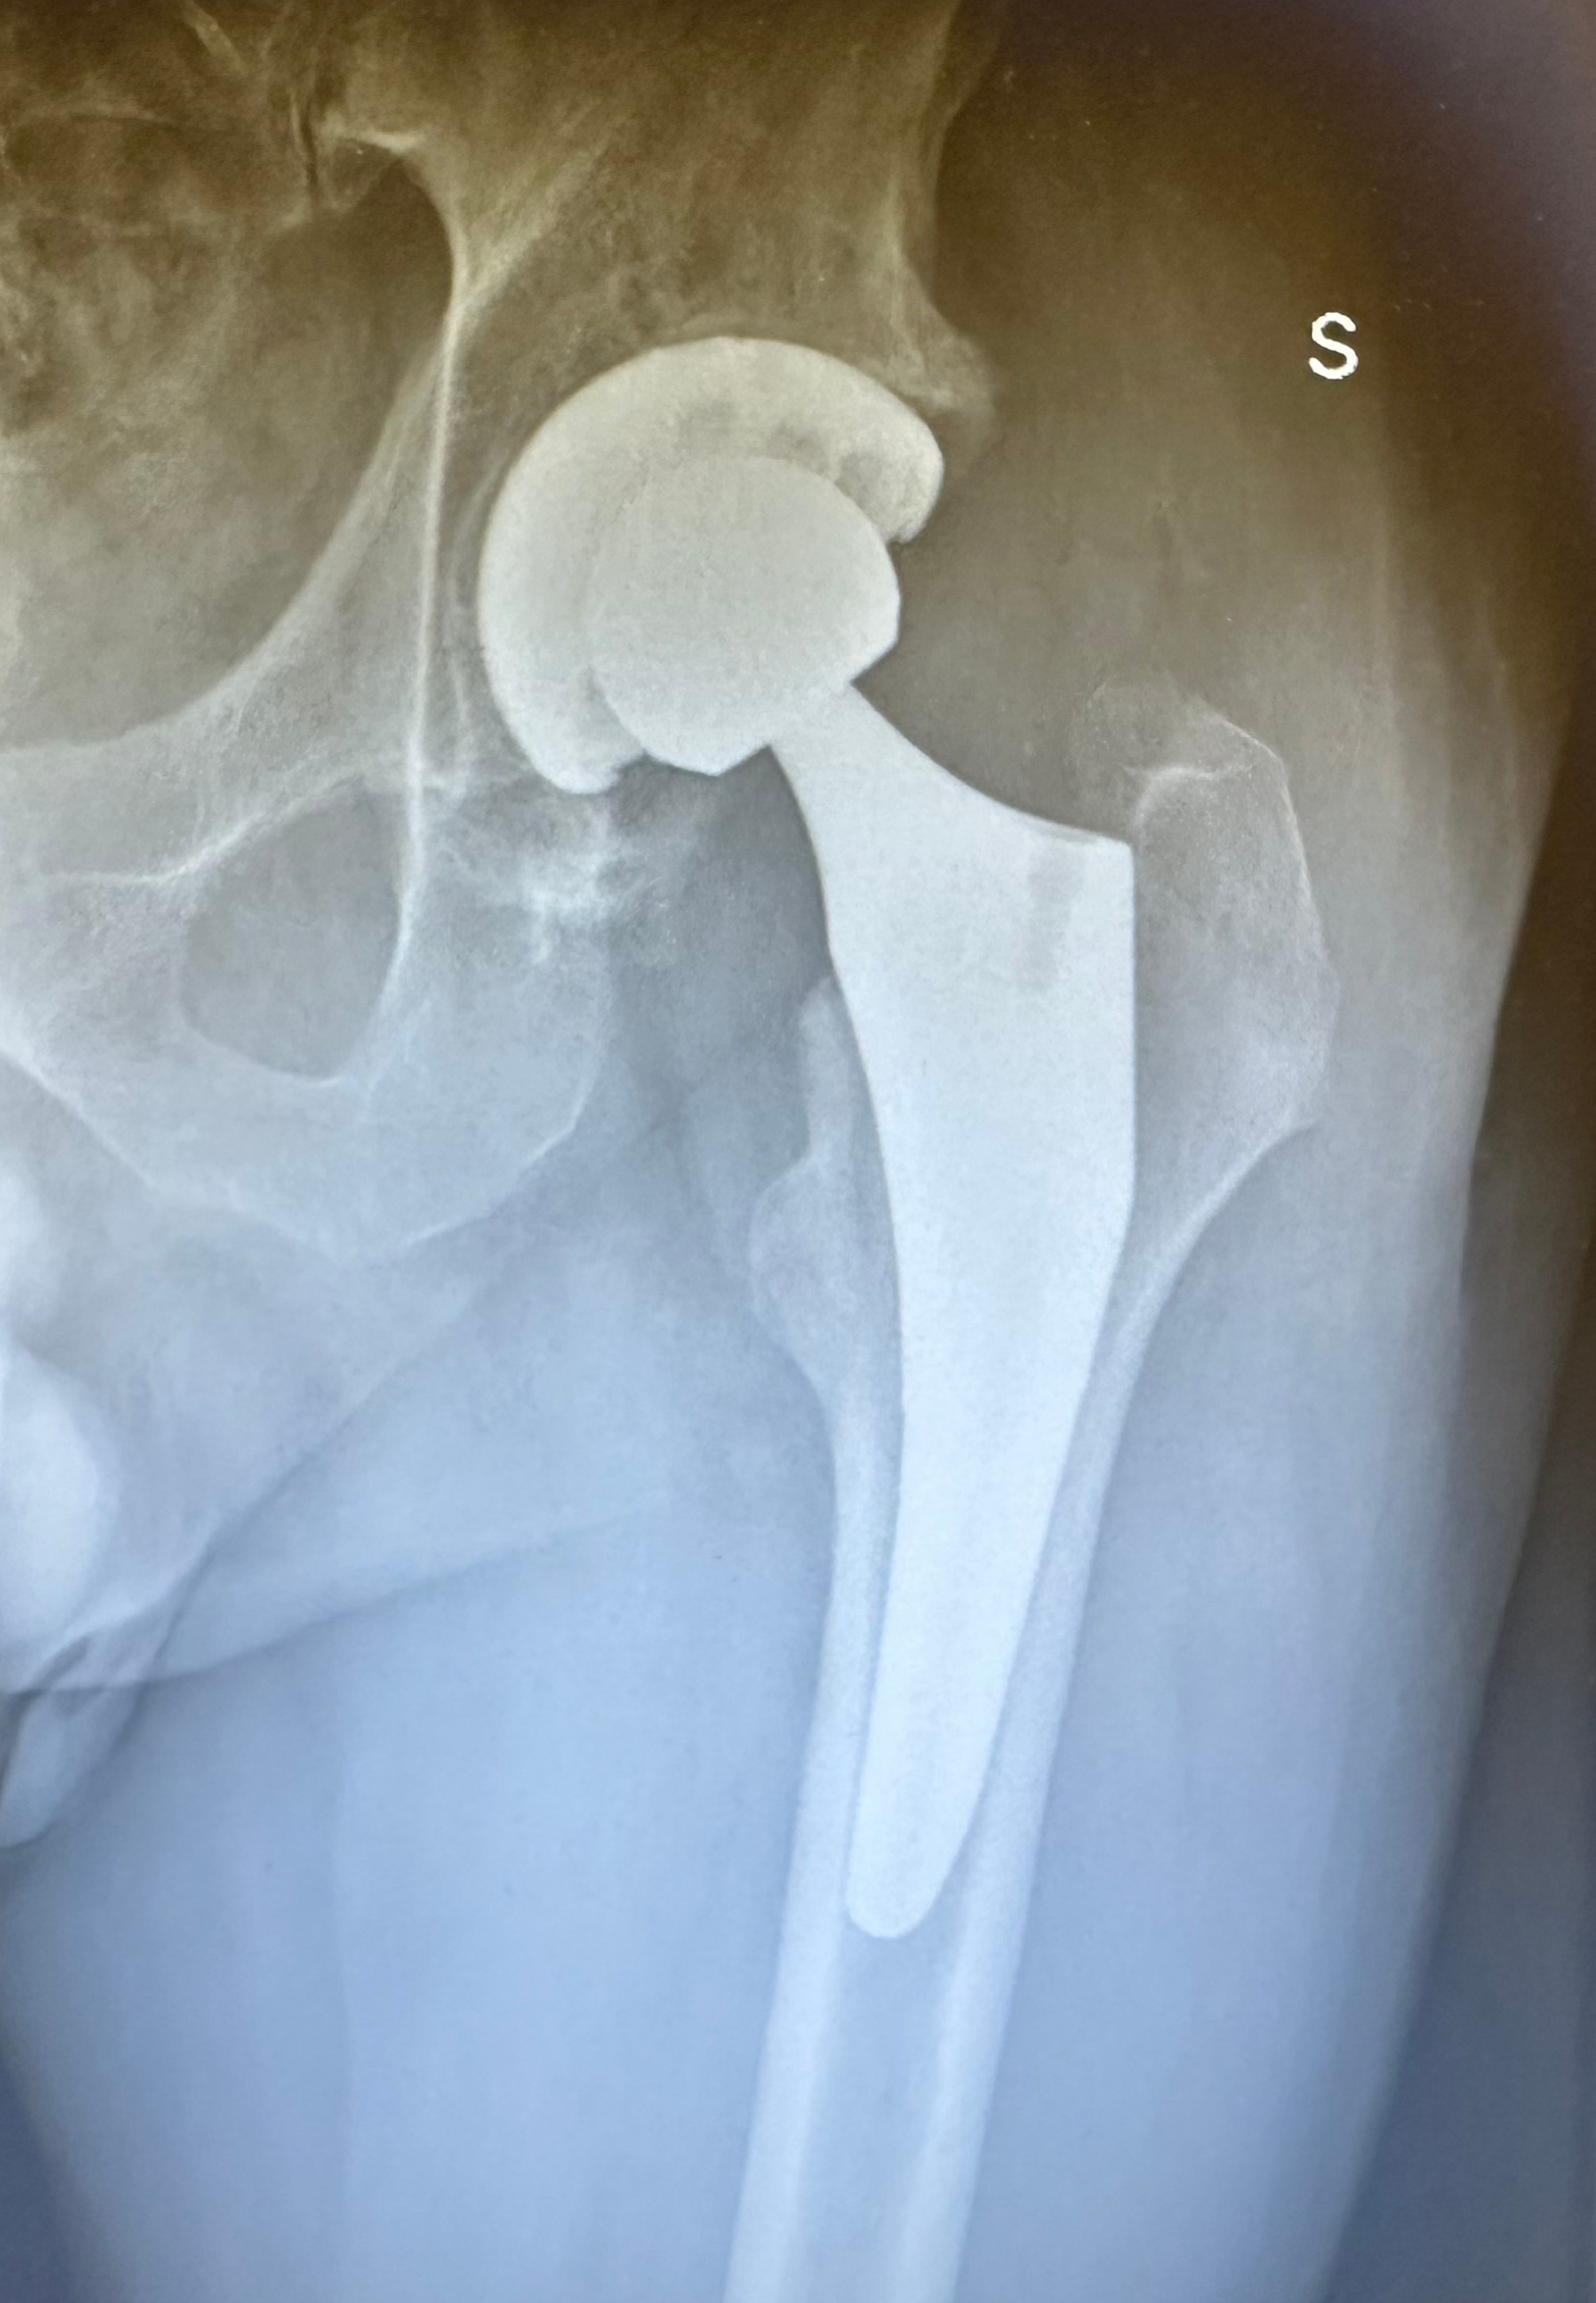

Protesi Totale d'Anca - proiezione AP.